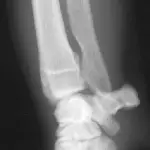

Figure 1A. Hairline fracture of the fibula.

Figure 1B. The fracture is more clearly seen 4 weeks later following bone resorption and periosteal proliferation at the fracture site.